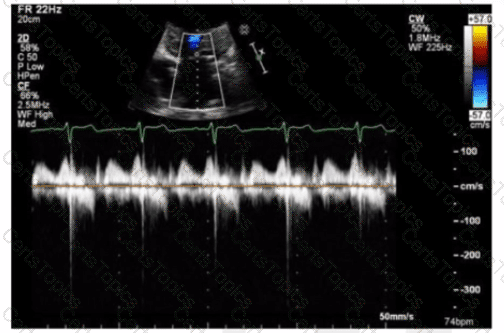

The sonographer obtains this Doppler signal while using the non-imaging transducer in the apical position. What is the best way to differentiate between mitral regurgitation and aortic stenosis signals in the waveform shown in this image?

Which Doppler signal is most consistent with significant aortic valve regurgitation?